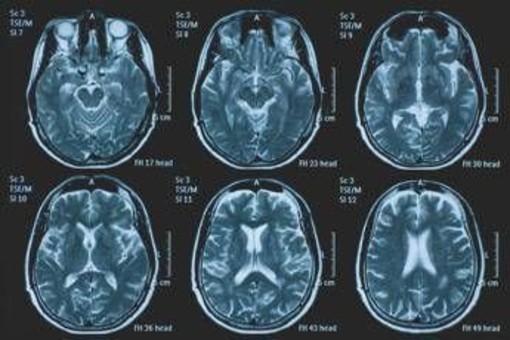

(Adnkronos) - La Commissione europea (Ce) ha autorizzato la commercializzazione condizionata di tovorafenib come monoterapia per il trattamento dei pazienti di età pari o superiore a 6 mesi con glioma pediatrico di basso grado che presentano una fusione o un riarrangiamento del gene Braf o una mutazione Braf-V600, in progressione di malattia dopo una o più terapie sistemiche precedenti. Lo annuncia Ipsen, in una nota, precisando che si tratta della “prima terapia mirata” per questa patologia e che la decisione della Ce si riferisce ai 27 Stati membri della Ue, oltre a Islanda, Liechtenstein e Norvegia. Ogni anno in Ue vengono diagnosticati più di 800 nuovi casi di glioma pediatrico di basso grado (pLgg) con alterazione di Braf. Questo tumore cerebrale, nonostante sia classificato di basso grado (a lenta progressione), comporta un carico significativo e permanente che accompagna la persona per tutta la vita, causando spesso importanti compromissioni fisiche e neurologiche, tra cui perdita della vista, difficoltà di linguaggio e disfunzioni motorie, che possono incidere in modo significativo sull’istruzione, l’autonomia e la qualità di vita a lungo termine del bambino. Finora, molti bambini con pLgg hanno dovuto sottoporsi a interventi chirurgici invasivi, a più cicli di chemioterapia e a radioterapia, con conseguenti complicazioni della salute.

L’approvazione della Ce si basa sui dati dello studio di fase 2 Firefly-1 che ha valutato tovorafenib in 137 bambini e giovani adulti con pLgg recidivato o refrattario con alterazioni di Braf che avevano ricevuto almeno una precedente terapia sistemica. Nel dettaglio, lo studio ha dimostrato una risposta tumorale clinicamente significativa con un tasso di risposta globale del 71% secondo i criteri Rano-Hgg (ResponseAssessment in Neuro-Oncology criteria for High-Grade Gliomas) e del 53% secondo i criteri Raono-Lgg (Response Assessment in Paediatric Neuro-Oncology for Low-Grade Glioma), con un tasso di beneficio clinico del 77% secondo i criteri Rano-Hgg e del 58% secondo i criteri Rapno-Lgg. Le risposte - riferisce la nota - sono state rapide e durature: sulla base dei criteri Rapno-Lgg, tra coloro che hanno risposto, il tempo mediano alla risposta è stato di 5,4 mesi con una durata mediana della risposta di 18 mesi.